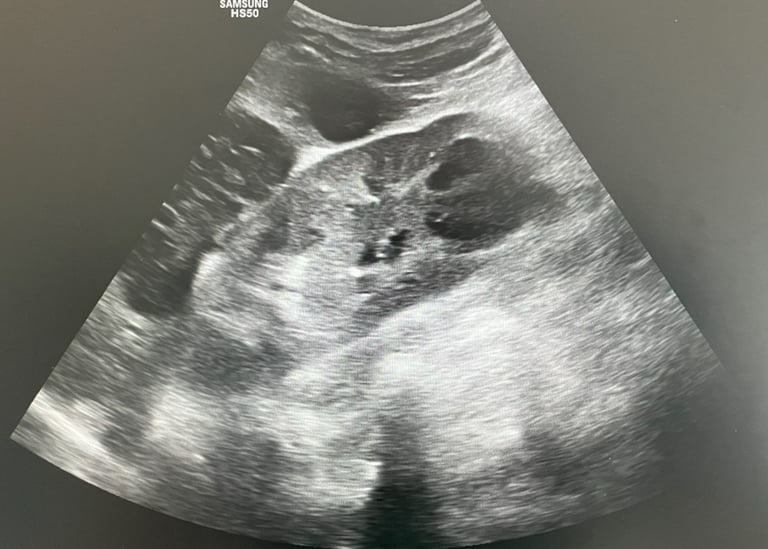

Apendicită acută - aspect ecografic sugestiv